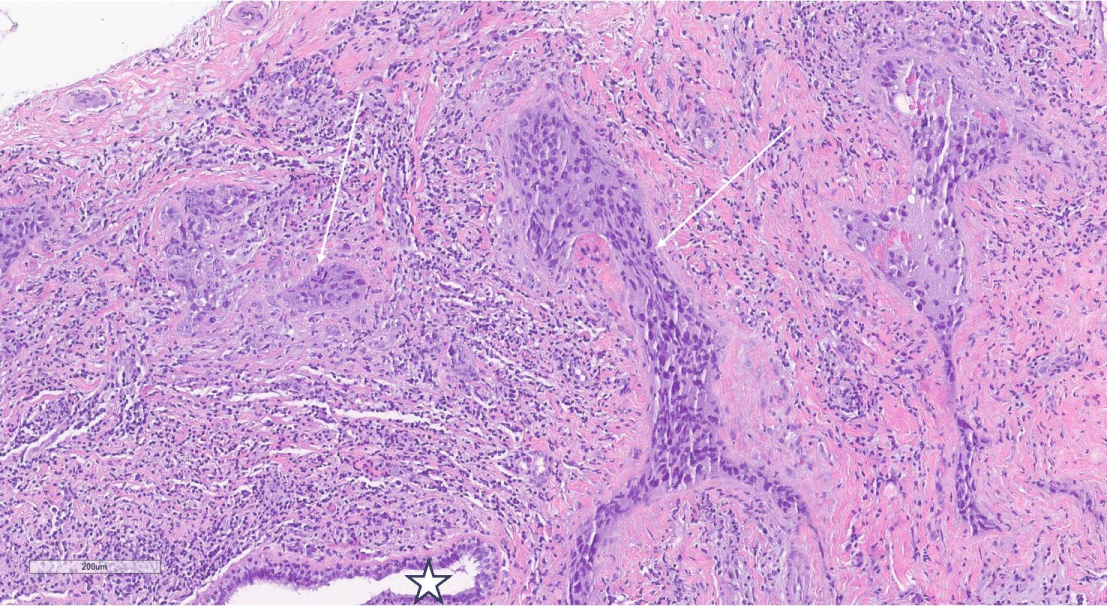

Figure 5: H&E, 10 X magnification of femur core biopsy showing fibrous dysplasia demonstrating abnormal proliferation of stellate fibroblasts (star) interspersed between woven bone with absence of osteoblastic rimming (arrows). View Figure 5

A 55-year-old woman presented to our tertiary care facility referred from an outside institution after a 3 cm mass in her left breast was identified (Figure 1). The mass was biopsied, and she was subsequently diagnosed with a high grade invasive ductal carcinoma (IDC) (Figure 2). The cancer was negative for estrogen receptor, progesterone receptor and Her2. Additionally, the proliferative rate as assessed by Ki-67 was 85 percent. An axillary lymph node was suspicious by imaging, but not biopsied. A nuclear medicine bone scan with a Tc-99 m radiotracer was used to stage her cancer (Figure 3). The imaging showed increased radiotracer uptake in the right proximal femur and right distal tibia suggestive of metastases and therefore, the patient was considered to have stage IV metastatic breast carcinoma. However, radiographs of the right femur and tibia showed stable lesions without aggressive cortical involvement and a ground glass appearance suggestive of fibrous dysplasia (Figure 4A and 4B). A subsequent biopsy of the proximal femur lesion showed atypical fibrous tissue with S-shaped woven bone trabeculae that tested negative for MDM2 amplification, essentially ruling out low grade osteosarcoma which can sometimes histologically mimic FD [11] and confirming the imaging impression of fibrous dysplasia (Figure 5). Additional genetic testing showed that the fibrous dysplasia was caused by a somatic mutation on codon 201 of the GNAS gene, substituting cytosine in CGT for thymine (TGT). As the fibrous dysplasia was found incidentally as part of the patient’s metastatic work up and was generally asymptomatic, it was clinically followed. Her triple negative breast cancer responded to preoperative chemotherapy, and a subsequent left breast segmental mastectomy showed only treatment related changes and no residual disease. The sentinel lymph nodes were negative for metastatic carcinoma. The breast specimen was evaluated by molecular sequence analysis which revealed no mutation in exon 8 or 9 of the GNAS gene. The patient is currently well with stable polyostotic fibrous dysplasia and without residual carcinoma.